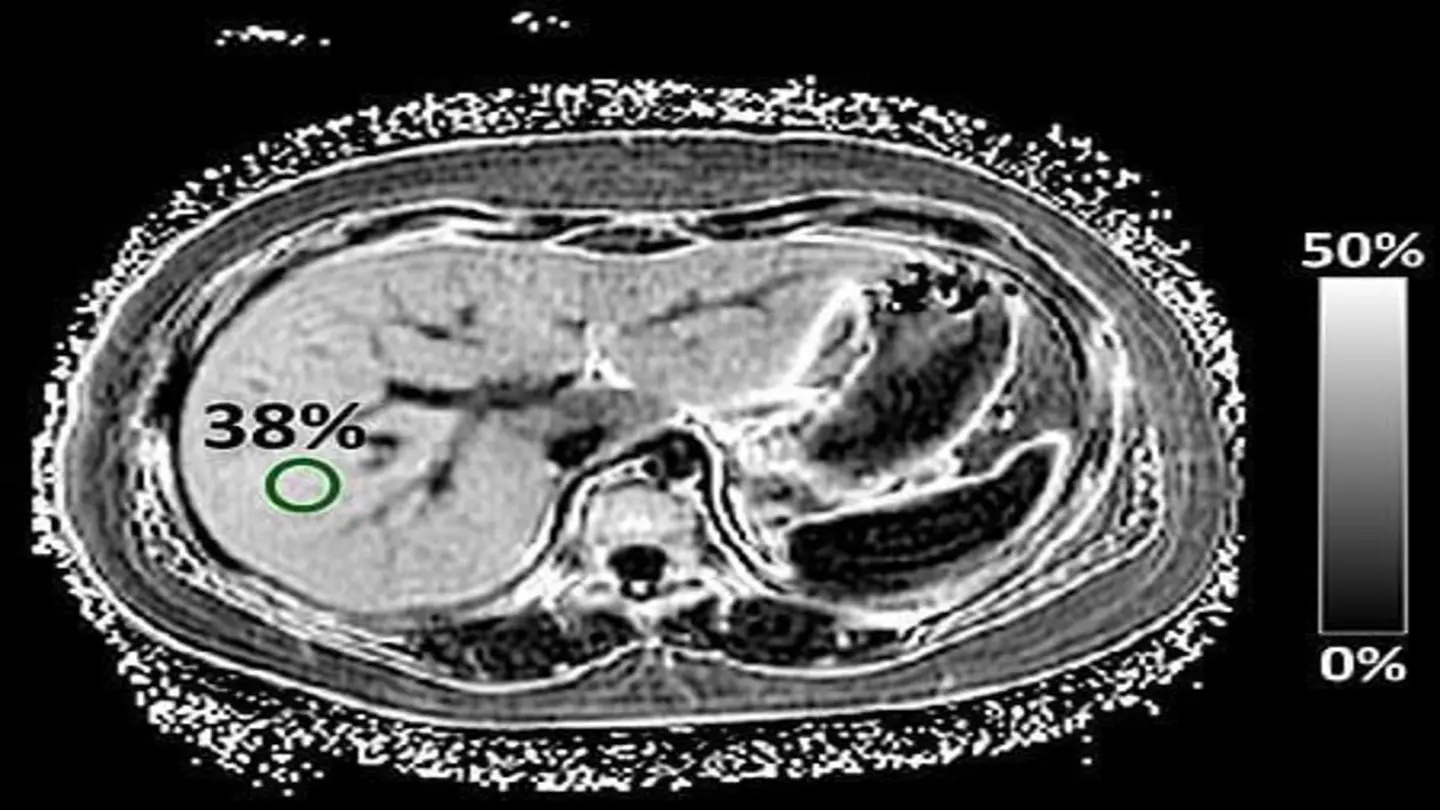

Image Source: Google | Image Credit: Respective Owner